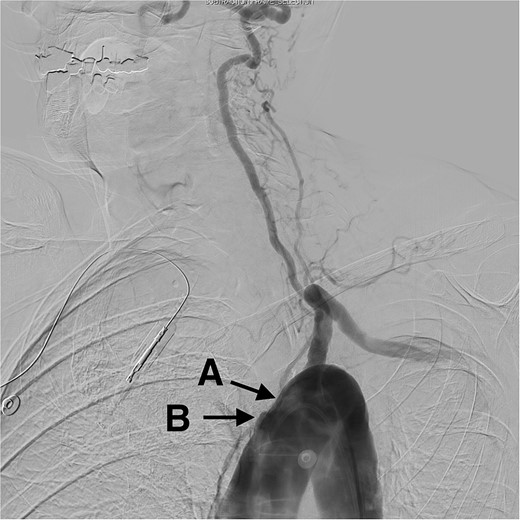

A cerebral angiogram demonstrated left common carotid occlusion (Fig. 1A) and the occlusion of the origin of the right brachycephalic trunk (Fig. 1B). Consequently, the left vertebral artery is the only cerebral vessel from the aortic arch filling anterogradely, resulting in retrograde flow to the brachycephalic trunk and of the right common carotid artery and right vertebral artery (Fig. 2A–D). The left internal carotid artery is filled from the left occipital artery, which is filled by the left vertebral artery. Intracranially the patient has the posterior communicating artery and the anterior communicating artery.

Digital subtraction angiogram demonstrating: (A) anterograde flow in the left vertebral artery and contrast going through the basilar formation. (B) Retrograde flow in the right vertebral artery. (C) Contrast reaching the right subclavian artery. (D) Anterograde flow in the right common carotid artery.